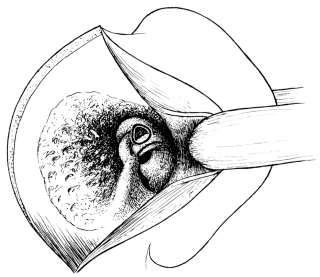

| 135. | Mules’s Operation. First step | 258 |

| 136. | Mules’s Operation. | 258 |